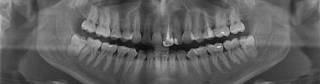

Ортопантомограмма — это вид панорамного исследования челюстей и зубов, позволяющий получить визуальную картину костных тканей. При минимальной рентгенологической нагрузке на пациента, ортопантомограмма поможет добиться качественных снимков с большим обзором.